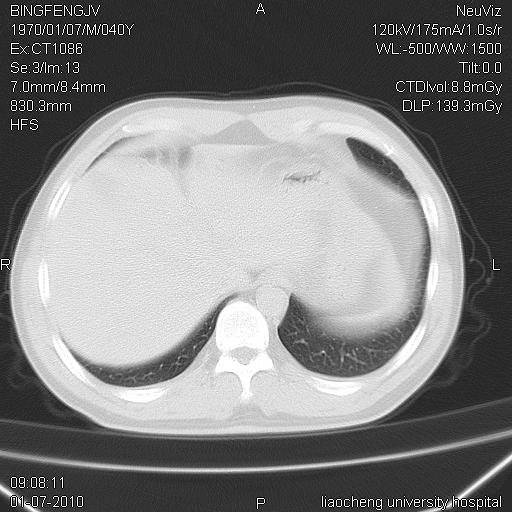

标题: CT23764B:男 40 肺部CT [打印本页]

标题: CT23764B:男 40 肺部CT

治疗2周后

炎症性病灶,继发性改变。

考虑左肺上叶近胸膜下炎症并肺气囊形成。

炎症,大部吸收。